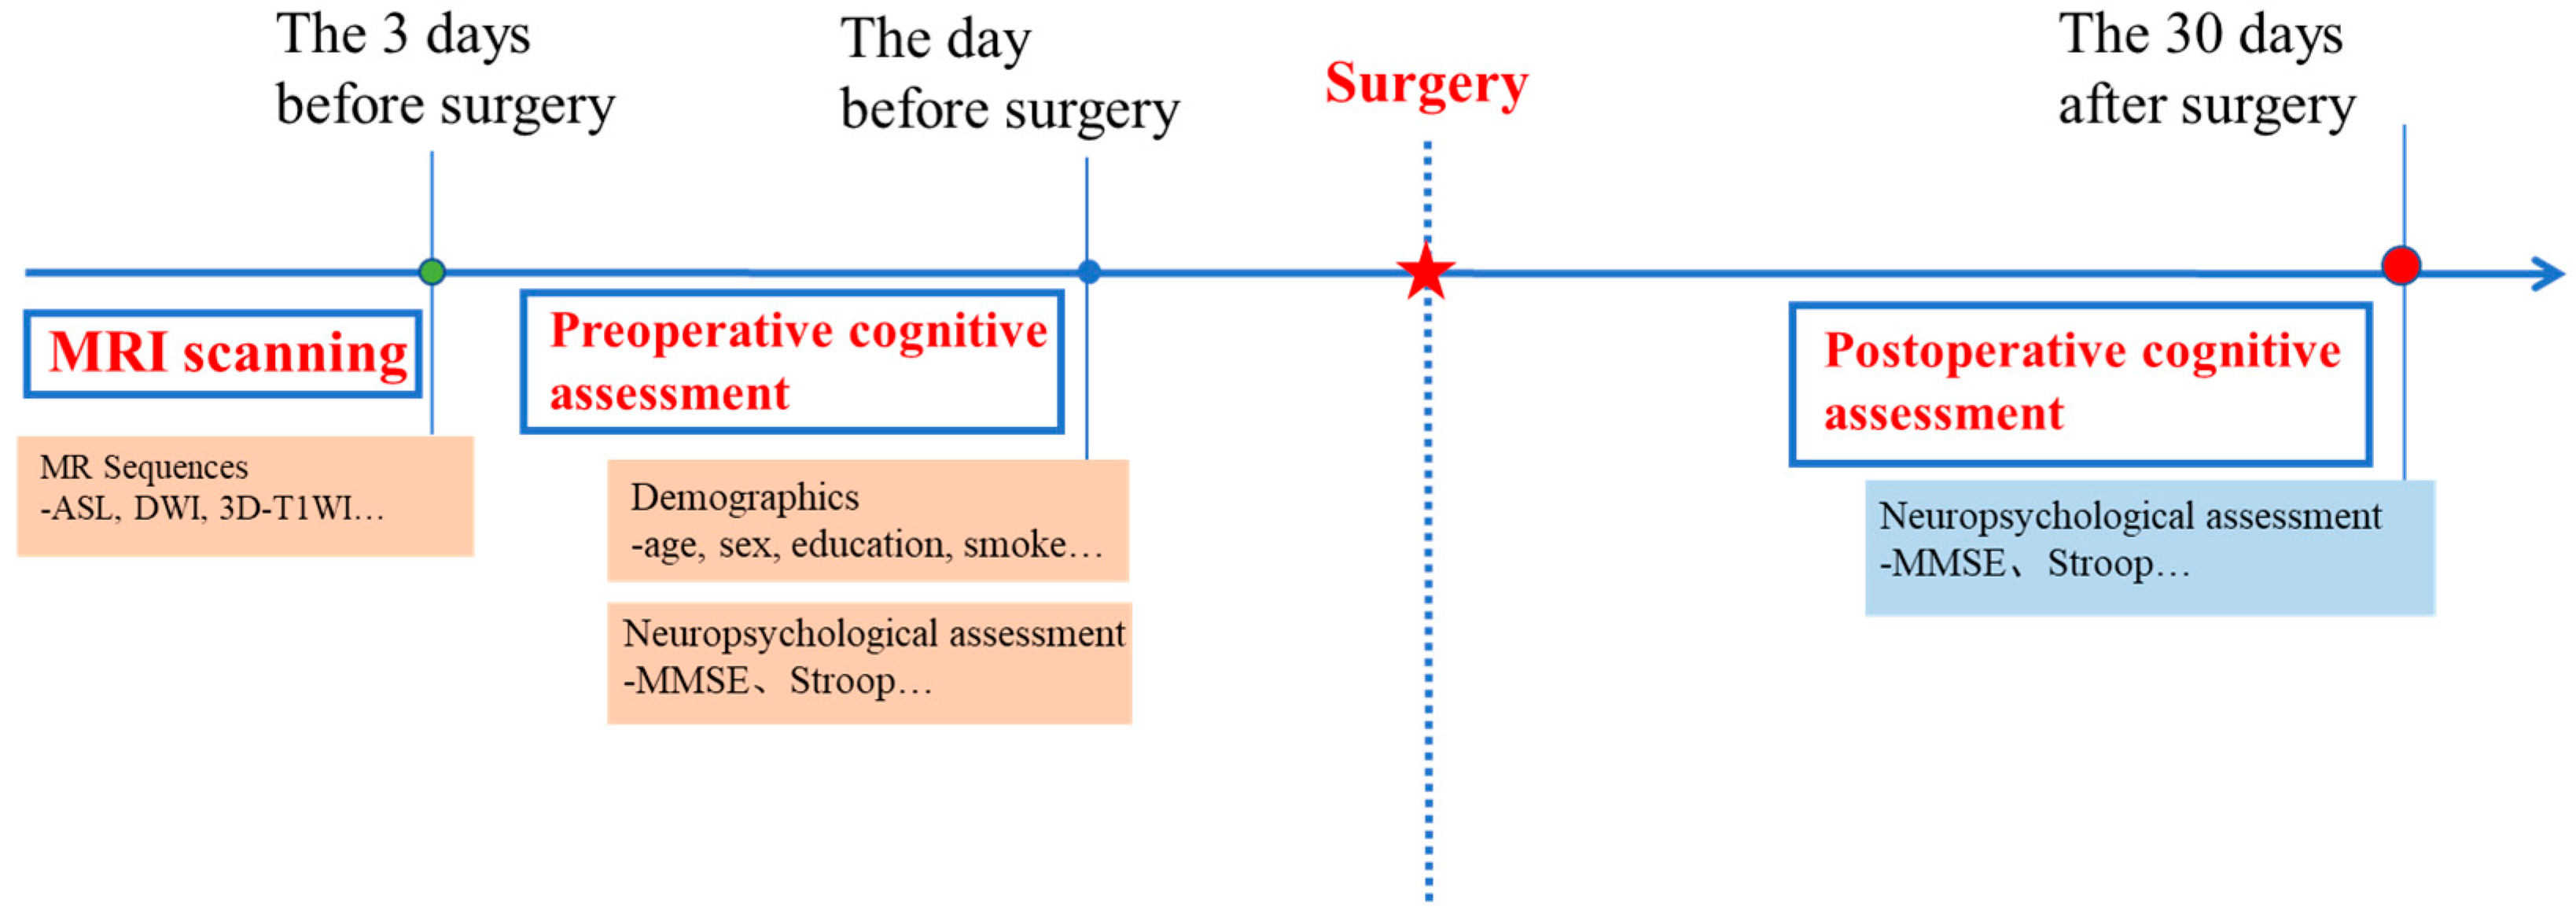

2.2. Study Processes

2.3. Neuropsychological Evaluation and POCD Definition

2.4. MRI Scan